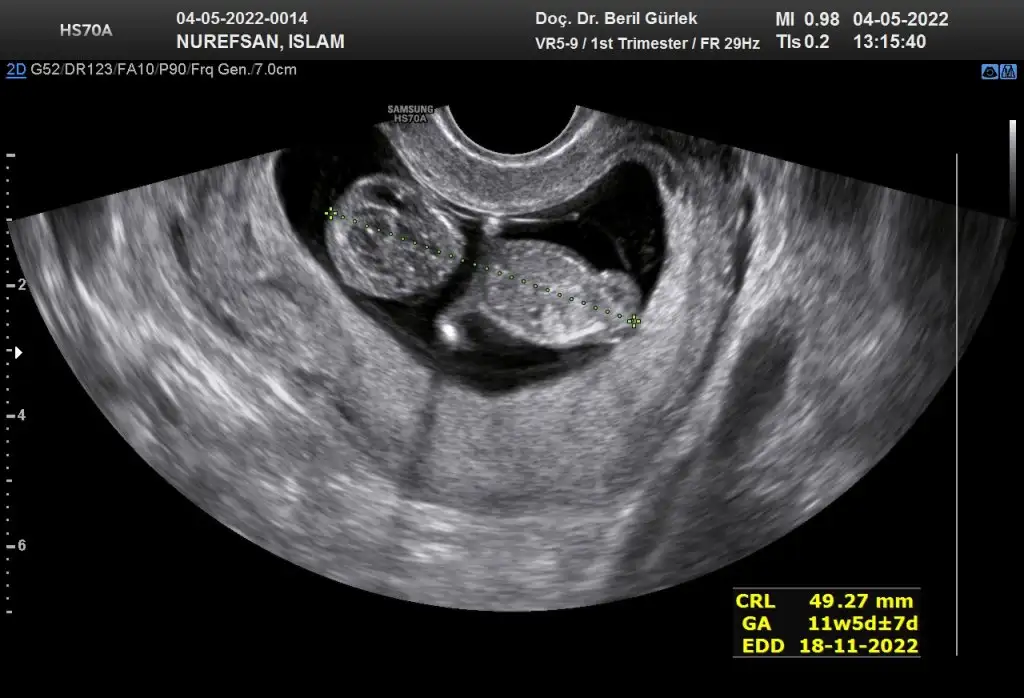

erkek gibi11+4 tahmin edebilir misinizzzz